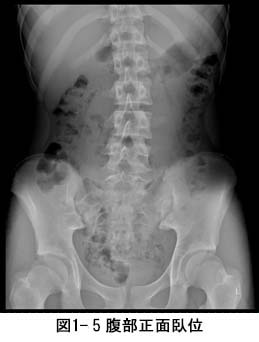

ˆê”ÊŽB‰e‚Æ‚ÍAXüŽB‰eiƒŒƒ“ƒgƒQƒ“ŽB‰ej‚Ì‚±‚Æ‚ÅAŽB‰e•”ˆÊ‚ÉXü‚ƌĂ΂ê‚é•úŽËü‚̈êŽí‚ðÆŽË‚µ‚ÄŽB‰e‚µ‚Ü‚·BŽÊ^‚©‚ç‚ÍA”x‚Ìó‘Ԃ✂̌`ó‚ȂǂðŠÏŽ@‚·‚邱‚Æ‚ª‚Å‚«‚Ü‚·B

“–‰@‚Å‚Í3•”‰®‚ ‚éŽB‰eŽº‚Ì‘S‚Ä‚ÅAƒtƒ‰ƒbƒgƒpƒlƒ‹ƒfƒBƒeƒNƒ^iFPDj‚ƌĂ΂ê‚éÅV‚Ì‘•’u‚𓱓ü‚µ‚Ä‚¢‚Ü‚·i}1-2jB‘S‚Ẳ摜‚ðƒfƒWƒ^ƒ‹‚ň—‚·‚邱‚Ƃɂæ‚èAŒŸ¸ŽžŠÔ‚Ì’Zk‚Æ”í‚΂‚̒ጸ‰»‚ð}‚Á‚Ä‚¢‚Ü‚·B